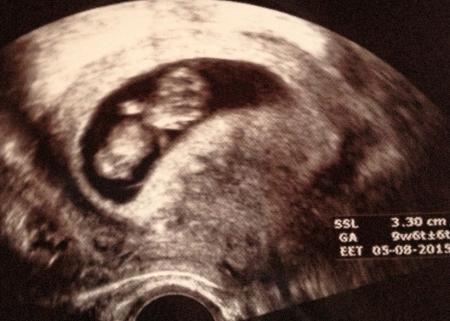

Hi ihr Lieben Ich hatte gestern auch endlich meinen zweiten FA Termin. Ich War so aufgeregt ob alles okay ist. Dem kleinen Gummibärchen geht es super. Alles dran, zeitgerecht entwickelt , Herz hat geschlagen und es hat ordentlich gezappelt. Ich hab gleich drei Bilder bekommen. Meine Fa könnte sich nicht entscheiden welches das beste ist. Ich muss echt sagen ich hab so eine tolle Ärztin. Sie freut sich immer richtig mit und ich bekomme immer tolle Bilder. Mit meiner Übelkeit ist es auch viel besser. Kugel morgen in die 11. Woche ☺ wie geht es euch? Lg

Das Bild

Bild zu